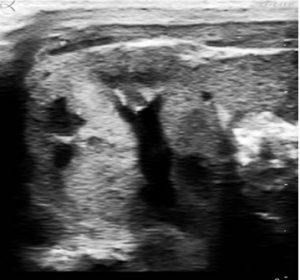

Hình 1: mặt cắt ngang thận phải của một bé sơ sinh đẻ non 34 tuần. Giãn ứ dịch áp lực thấp của một đài thận lớn và hình ảnh phản âm nhẹ ở một nhú thận.

Tôi đã chọn một hình siêu âm từ lần ghé thăm khoa NICU tầng III. Trong số những tiến bộ gần đây của siêu âm là tạo ra hình ảnh có độ phân giải cao, độ tương phản cao bên trong một lồng ấp mà không làm ảnh hưởng gì đến bé non tháng nhẹ ký ở trong đó. Khảo sát siêu âm được chỉ định theo yêu cầu khi có nghi ngờ về bệnh lý. Thường thì không có hình ảnh chuẩn cho việc so sánh hoặc sàng lọc trước cho chẩn đoán sớm.

Hình ảnh siêu âm của thận của bé gái non tháng được xác định thuộc nhóm chứng bình thường, không có kèm thông tin gì khác thêm. Tại thời điểm đó, từ hình ảnh này và cho rằng hình dạng giống nhau của các nhú thận khác trên cả hai thận. Với lối ứng xử nhanh thì có thể đoan chắc rằng: báo động mức màu vàng- có cái gì đó khác thường và ít gặp, có thể là bệnh lý. Cũng có hồi chuông cảnh báo vấn đề là tại chỗ và nguyên nhân có thể là do tác dụng phụ của thuốc. Còn đối với lối ứng xử chậm thì sẽ không thể suy luận thêm khi không có thêm thông tin nào khác; chẳng hạn là tại sao đứa bé này bị sinh non và thai có bị đa ối không? Tiếp đó, lối ứng xử chậm đòi hỏi khai thác đầy đủ tất cả thông tin lâm sàng, nó muốn xem xét lại các bệnh lý thận ở trẻ sơ sinh được biết. Phải chăng biểu hiện hình ảnh là chỉ dấu cho bệnh vôi hóa tủy thận hay chỉ điểm cho hoại tử nhú thận? Hay có phải hình ảnh trở lại bình thường cùng với quá trình hồi phục nhanh ở thai hay ở sơ sinh? Hiện tại vẫn chưa có bất kỳ dữ liệu có sẵn để biết mức độ nặng của các hình ảnh thu được liên quan đến đặc điểm phát triển sau này của thận ở trẻ nhi hay của chức năng thận ở tuổi thiếu niên lẫn thanh niên. Chỉ với một hình siêu âm rất rõ nét của tháp thận đã làm gia tăng mối quan tâm của Daneman và cộng sự trong bài báo trên tập san Radiographics - Tháp thận: hình ảnh siêu âm bình thường và quá trình bệnh lý.